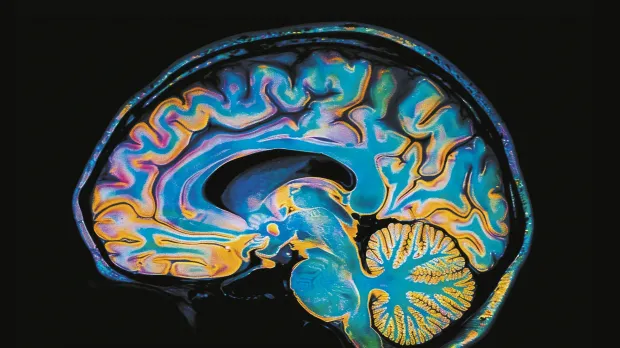

Maladies neuro-dégénératives : quand le cerveau ne répond plus